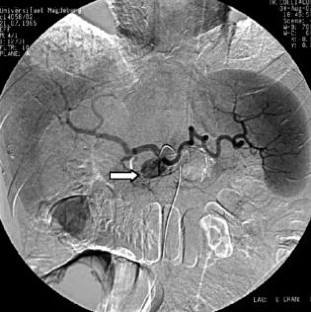

Wir berichten über das diagnostische und therapeutische Vorgehen anhand von 7 Patienten mit Blutungen aus der A. gastroduodenalis (n=5) nach pankreaschirurgischen Interventionen bei Pankreaskopfkarzinom, Rezidiv eines Liposarkoms und chronischer Pankreatitis, der A. hepatica communis (n=1) bei chronischer Pankreatitis und der A. mesenterica superior (n=1) nach akuter Pankreatitis. Anhand von 4 Kasuistiken werden unsere Erfahrungen mit der Implantation von Stentgrafts (Hemobahn®-Prothesen) vermittelt. Den Vorteil der Stentgrafts sehen wir in der sofortigen Blutstillung bei fehlendem Kontakt der Endoprothese zu infiziertem Gewebe und Erhalt der Perfusion des abhängigen Organs. Unsere positiven Erfahrungen mit diesen interventionellen Therapieverfahren erfordern jedoch weitere klinische Untersuchungen, wobei im Mittelpunkt die Indikationen, die technische Erfolgsrate, die stentbedingten Komplikationen und die Langzeitverläufe stehen sollten.

Spontaneous or postoperative hemorrhage into the abdominal cavity due to inflammatory vessel arrosion represents an uncommon but menacing situation. According to the literature, such hemorrhage is associated with a lethality of nearly 2%. Therapeutical options include reoperation and interventional radiological techniques such as endovascular catheter techniques with stent graft implantation or the embolization of vessels. We report on the management of seven cases with hemorrhage either from the gastroduodenal artery (n=5) following pancreatic surgery for pancreatic carcinoma, liposarcoma, and chronic pancreatitis or from the common hepatic artery (n=1) and the superior mesenteric artery (n=1) following chronic pancreatitis. The present article describes our experiences with stent graft implantation (hemobahn prosthesis) in four cases. Based on these experiences, we see the advantages of stent grafts in primary hemostasis without any contact to infected tissue and the preservation of regular perfusion. However, further clinical data are required focussing on indication, technical success rates, stent-related complications, and long-term outcome.